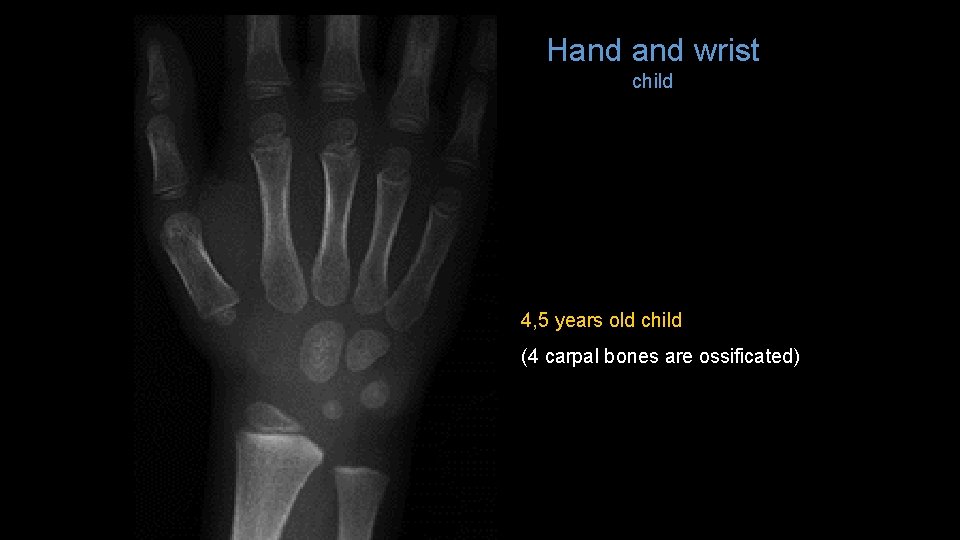

Hand wrist child 4, 5 years old child (4 carpal bones are ossificated)